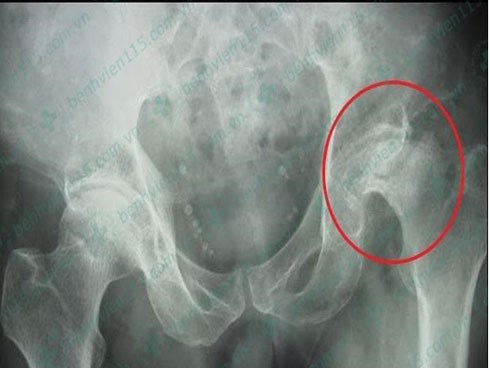

Hoại tử chỏm xương đùi vì uống rượu, hút thuốc quá nhiều

Mới đây, BV Nhân dân 115 TP.HCM tiếp nhận ông VVT (46 tuổi, ở TP.HCM) trong tìnhtrạng đau khớp gối cùng bên khớp háng phải.